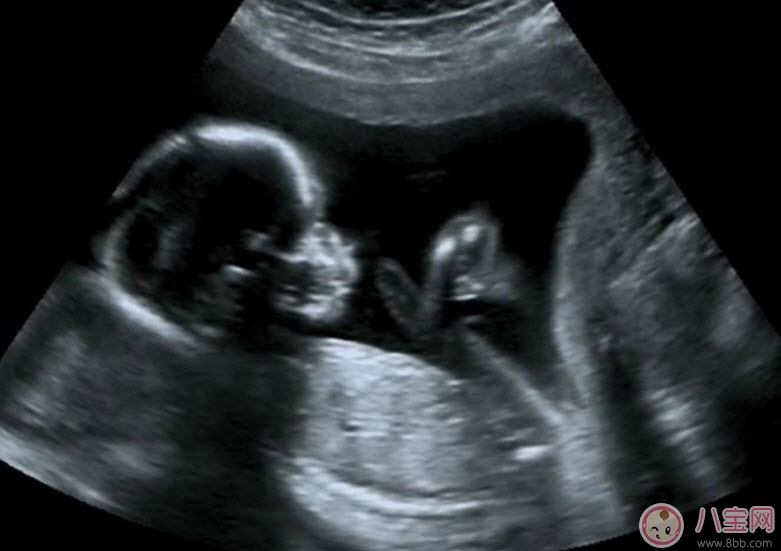

為監(jiān)測孕囊的部位、胎兒的生長發(fā)育情況,降低畸形兒和有缺陷兒的出生率,早孕期陰道B超檢查顯然是很必要的。早孕期做陰道B超檢查有以下幾點好處:

1.清楚地了解孕囊的位置是否正常,明確是宮內(nèi)還是宮外妊娠(俗稱宮外孕)。

2.核實孕周、判斷胚胎發(fā)育情況。根據(jù)孕囊的平均直徑、胎芽大小、胎兒的頭臀長判斷孕齡,有助于中晚孕期間判斷胎兒發(fā)育的狀況。經(jīng)陰道B超胎芽大于5mm時,應(yīng)該見到胎心搏動。如果沒有見到胎心搏動,提示有胚胎停止發(fā)育 的可能,應(yīng)定期復(fù)查。

3.判斷胚胎的數(shù)目,這是早期診斷是否多胎妊娠的最準確的方法。

4.觀察胎盤的早期發(fā)育。妊娠6周時,胚胎的葉狀絨毛膜與子宮的底蛻膜開始形成原始胎盤,妊娠8周,就可以辨認出胎盤了。

5.及早發(fā)現(xiàn)子宮、附件的異常。了解是否有子宮畸形、肌瘤以及附件區(qū)腫物等等。

由此可見,B超的確在早孕的診斷與疾病的鑒別診斷方面有重要的應(yīng)用價值。